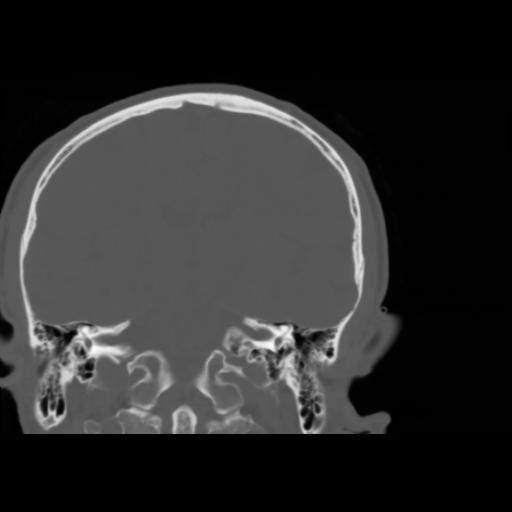

5 CEREBRO,,Coronal,3.000,CEREBRO,Coronal,